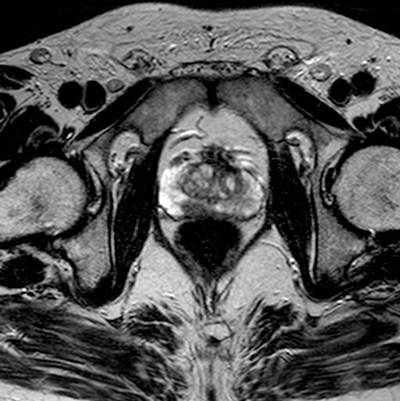

Seventy percent of prostate adenocarcinomas arise in the peripheral zone [4]. On T2-weighted images, prostate cancer appears as a low signal intensity area within the normally hyper-intense peripheral zone (Figure 3).

Figure 3: Axial T2 image showing area of low signal in the right peripheral zone in keeping with tumour.

Peripheral zone low signal, however, can occur in a variety of conditions, such as haemorrhage, prostatitis, benign hyperplastic nodules, or post-treatment change [4]. Post-biopsy haemorrhage, in particular can be an important confounding variable, and may hamper tumour detection. T1-weighted imaging plays an important role, as haemorrhage demonstrates high signal intensity on the T1W images, whereas tumour demonstrates low signal intensity on T1W. Generally a delay of six to eight weeks post-biopsy is also recommended to allow for resolution of haemorrhage. Dynamic contrast enhanced imaging and diffusion-weighted imaging (DWI) can also aid in distinguishing tumour from benign conditions.

Although MR is most accurate in the detection of peripheral zone tumours, central / transitional zone tumours should also be actively considered, especially in patients with rising PSA and multiple negative transrectal biopsies [2]. Given the commonly heterogeneous appearance of the central gland, MR interpretation may be difficult, but the presence of the following may aid diagnosis: homogenous low signal intensity in the central zone (especially in the absence of an obvious peripheral zone tumour), poorly defined or speculated margins, absence or interruption of the low-signal pseudocapsule or urethral invasion (Figure 4) [2].

Figure 4: Axial T2 image showing diffuse low signal in the left central zone.